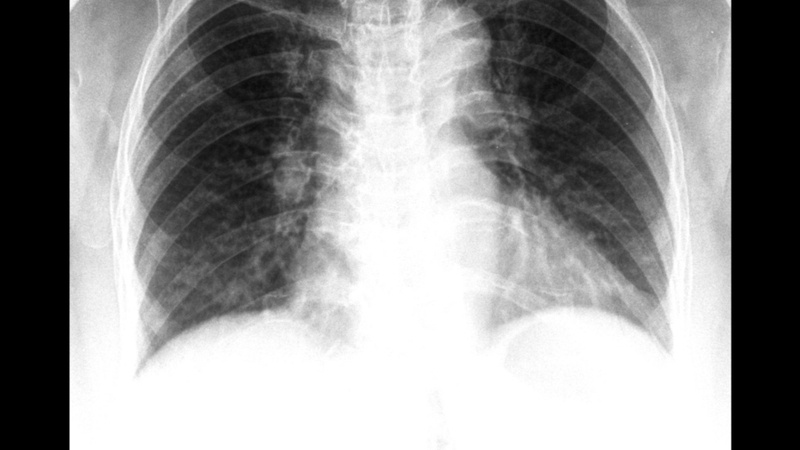

Chụp X quang viêm phổi do phế cầu là phương pháp chẩn đoán hình ảnh giúp bác sĩ phát hiện tổn thương phổi, xác định mức độ viêm và theo dõi tiến triển bệnh. Đây là bước quan trọng khi người bệnh có triệu chứng sốt cao, ho, đau ngực hoặc khó thở.

Chụp X quang bệnh viêm phổi do phế cầu là kỹ thuật sử dụng tia X để ghi lại hình ảnh phổi, giúp phát hiện các vùng phổi bị viêm, đặc biệt là hình ảnh đông đặc thùy phổi - dấu hiệu thường gặp trong viêm phổi do vi khuẩn phế cầu.

Viêm phổi do phế cầu (do vi khuẩn Streptococcus pneumoniae) thường gây tổn thương tập trung tại một thùy phổi. Trên phim X quang, bác sĩ có thể nhận thấy:

Những đặc điểm này giúp phân biệt viêm phổi do phế cầu với viêm phổi do virus (thường tổn thương lan tỏa hai bên phổi). Viêm phổi thùy là hình thái kinh điển của viêm phổi do phế cầu và X quang ngực là công cụ đầu tay trong chẩn đoán.

Chụp X quang viêm phổi do phế cầu là phương pháp quan trọng giúp bác sĩ chẩn đoán chính xác, đánh giá mức độ tổn thương và theo dõi hiệu quả điều trị. Hình ảnh điển hình là vùng đông đặc tại một thùy phổi, giúp phân biệt với các dạng viêm phổi khác. Gia đình người bệnh nên yên tâm khi được chỉ định chụp X quang, vì đây là kỹ thuật an toàn và mang lại lợi ích lớn trong phát hiện sớm biến chứng. Tuy nhiên, mọi quyết định điều trị và theo dõi cần được thực hiện theo hướng dẫn của bác sĩ chuyên khoa.